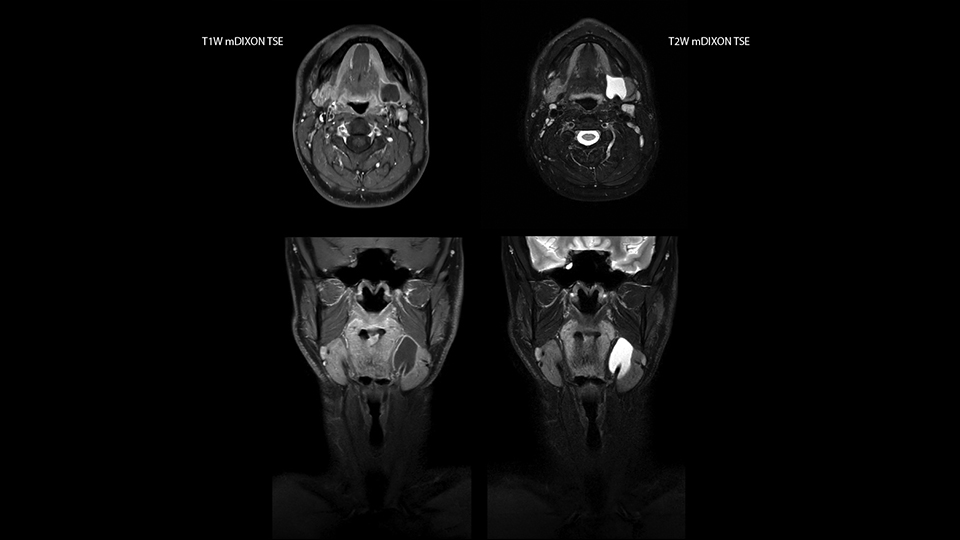

“Our DMG Lisle location includes a cancer center, so soft tissue neck scans, brachial plexus scans, and prostate scans are common. For these exams, mDIXON TSE provides excellent images with and without fat suppression all while helping us reduce repeats and work more efficiently,” Mr. Duffy says.

“With the 2-echo Philips mDIXON TSE the timing is short and the fatsat is very robust. The biggest thing is that you know your fat suppression will be good, even in thin patients or large patients that are off-center,” Mr. Sybesma says.

“mDIXON TSE raises our diagnostic confidence with its homogeneous

fat suppression. Neck exams and rheumatology patients are two examples where mDIXON TSE is especially useful,” Dr. Kaakaji says. “For us it’s also an efficiency boost in exams where we need pre and post T1-weighted images with great fat suppression.”